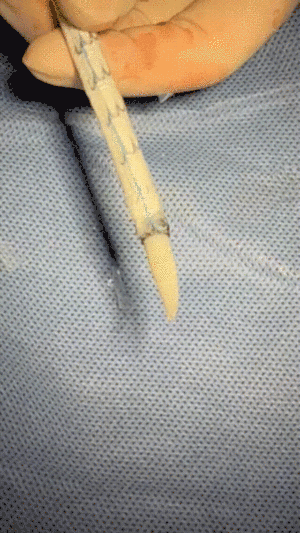

8. 修剪CADS支架TGM343420近端束缚膜,暴露局部裸区,争取更多锚定区。

修剪第一层膜

修剪第二层膜

修剪完成,暴露裸区